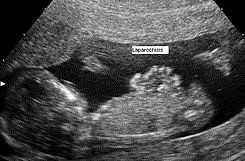

Gastrosquisis

El defecto es lateral al ombligo, por lo general a la derecha, en una región debilitada por la vena umbilical derecha, que en condiciones normales desaparece.

Es la herniación del contenido abdominal directamente en la cavidad amniótica a través de la pared corporal. Las vísceras no se hallan cubiertas por peritoneo ni por amnios y el intestino puede resultar dañado por contacto con el líquido amniótico. No está acompañada de otras anomalías cromosómicas u otros defectos graves y en consecuencia la tasa de supervivencia es excelente. Sin embargo, el vólvulo (rotación del intestino) que comprende la irrigación sanguínea puede destruir grandes porciones del intestino y provocar la muerte del feto.